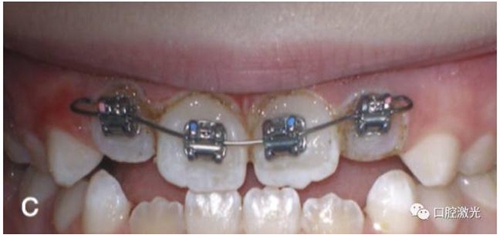

獲得理想的托槽粘接位置

正常情況下,理想的托槽粘接位置為牙冠的中心位置。如果要達到這一目的,正畸牙醫(yī)首先需要能夠從視覺上觀察清楚牙冠的整體形態(tài)。如果存在牙齦覆蓋、遮擋的情況,就很難達到這一目的。這時,簡單的激光牙齦切割就可以很好的增加牙冠的暴露程度,達到更加準確的粘接托槽的目的,從而也就加快了整個正畸療程的速度。通過下圖的病例可以看到,不僅患者節(jié)約了數(shù)月的等待時間,同時也創(chuàng)造了一個干凈的口腔環(huán)境,降低了在后續(xù)的正畸治療中可能導致牙齦增生的風險。

當天粘接托槽后即刻